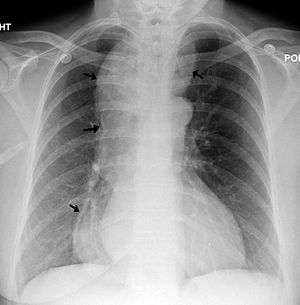

|

A chest X-ray showing achalasia ( arrows point to the outline of the massively dilated esophagus ) | |